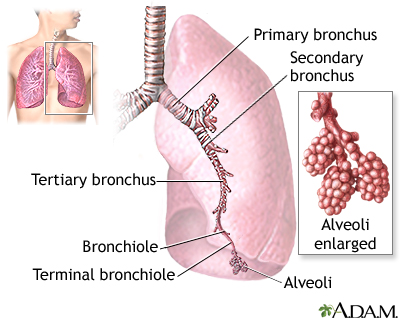

A collapsed lung occurs when air escapes from the lung. The air then can fill the space outside of the lung between the lung and chest wall. This buildup of air puts pressure on the lung, so it cannot expand as much as it normally does when you take a breath.